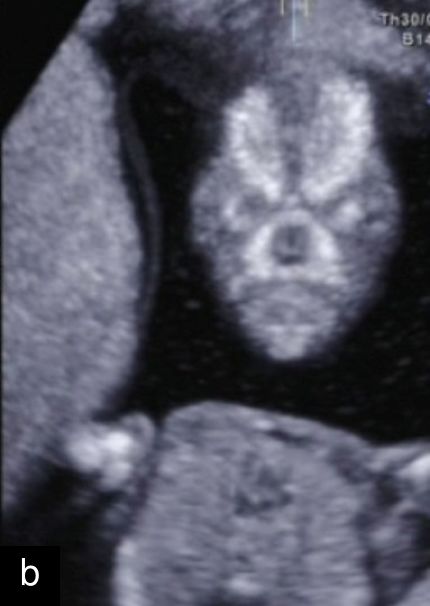

8

Ultrasound imaging of right-sided aortic arch at 12+3 weeks’ gestation using color Doppler (a) and spatiotemporal image correlation (b) modes.